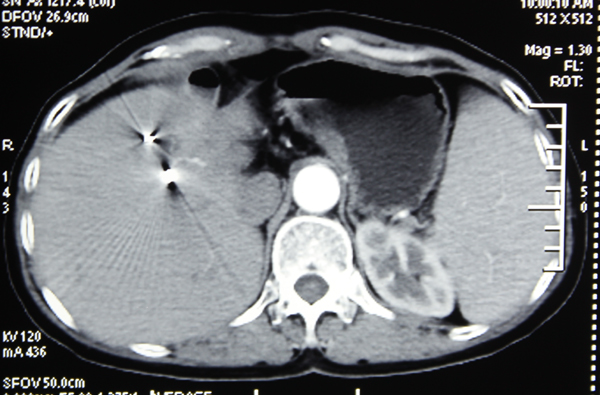

结合化疗、中药等中西医结合治疗方案,黄阿姨的病情在治疗1周后明显得到控制,肿块逐渐变小,疼痛感逐渐减轻……出院时疼痛已完全消失。今年3月,黄阿姨再次到我院进行复查,当她得知癌肿基本消失时激动万分……

肝癌射波刀治疗后肿块消失